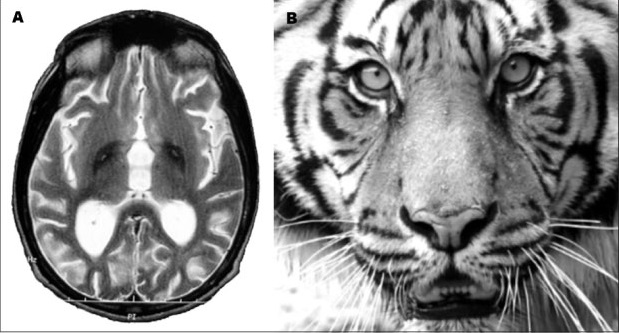

Заболевание считается редким: на 1 миллион человек приходится до 3 больных. Чаще всего это члены одного семейства. После обнаружения первых симптомов врачи проверяют пациентов с помощью магнитно-резонансной томографии (МРТ). Главным маркером расстройства является наличие на снимке так называемого «глаза тигра» – расположенная в области бледного шара гиперинтенсивная зона овальной формы, окруженная еще большей гипоинтенсивной зоной. Последняя представляет собой, собственно, «глаз», а гиперинтенсивная – его «зрачок». Этот эффект, как правило, возникает из-за избыточного накопления железа.